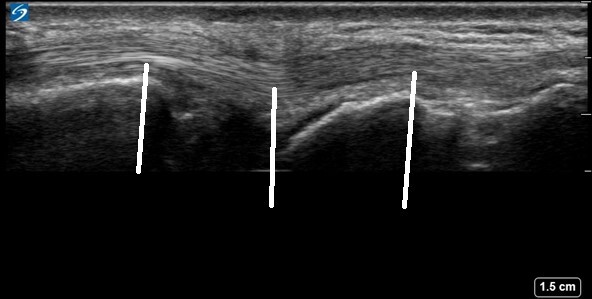

Wrist Compartment Six 2 Image

The lines point to the extensor carpi ulnaris